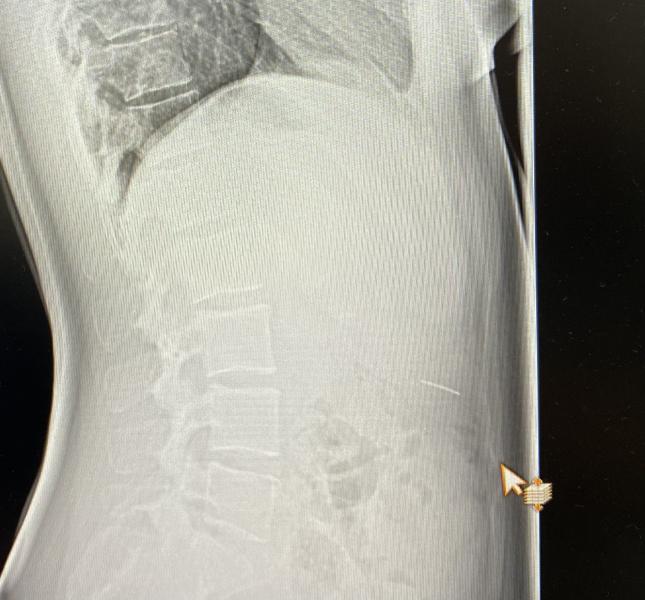

Проглотила кусок дуги от брекетов, кажите, что он выйдет сам. Приехала, в приемник, пока дождалась снимок, уже все низко спустилось, доставать не стали. Сейчас каждое болевое ощущение, у меня паника. Под ребрами сейчас было больно, но это же не оно точно?🤦🏼♀️

@nadin0407, ой, мне хирург нифига внятного не сказал) сказал, что низко уже, скорее всего выйдет) ну или заболит, приедете😆

Я замочек глотала от боекетов , но там не страшно , оно хотя бы не острый … но тоже переживала . По снимку кажется что см точно есть (((